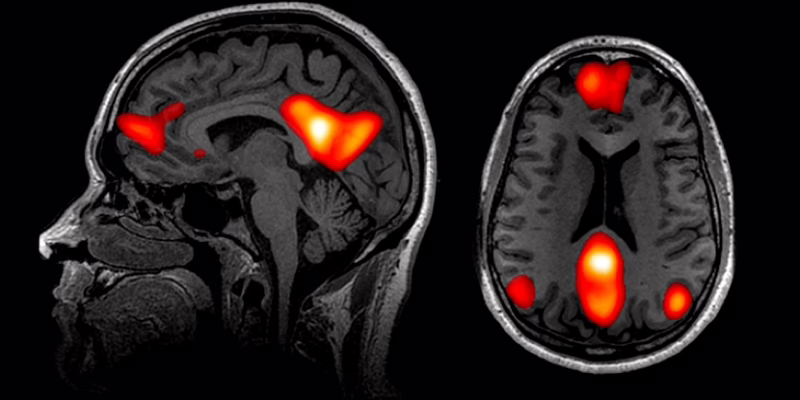

Коли ми відчуваємо нудьгу, наприклад, під час перегляду фільму, наш мозок задіює певні мережі. Мережа уваги надає пріоритет відповідним стимулам, відфільтровуючи відволікаючі фактори, і активна, коли ми починаємо дивитися фільм.

Однак, зі зменшенням нашої уваги, активність у мережі уваги знижується, що відображає нашу зменшену здатність підтримувати фокус на нецікавому контенті. Так само знижується активність у лобно-тім’яній або виконавчій контрольній мережі через труднощі з підтримкою зацікавленості у нецікавому фільмі.

Одночасно активується мережа режиму за замовчуванням, переключаючи нашу увагу на внутрішні думки та саморефлексію. Це основна функція мережі режиму за замовчуванням, яка називається інтроспекцією та вказує на стратегію подолання нудьги.

Ця складна взаємодія мереж включає кілька ключових ділянок мозку, які «працюють разом» під час стану нудьги. Острівцева мозкова оболонка є ключовим центром для сенсорної та емоційної обробки. Ця ділянка демонструє підвищену активність при виявленні внутрішніх сигналів тіла, таких як думки про нудьгу, що вказують на те, що фільм більше не захоплює. Це часто називають «інтероцепцією».

Мигдалину можна порівняти з внутрішньою системою сигналізації. Вона обробляє емоційну інформацію та відіграє певну роль у формуванні емоційних спогадів. Під час нудьги ця ділянка обробляє пов’язані з цим негативні емоції, а вентральна медіальна префронтальна кора мотивує нас шукати альтернативні стимулюючі заняття.